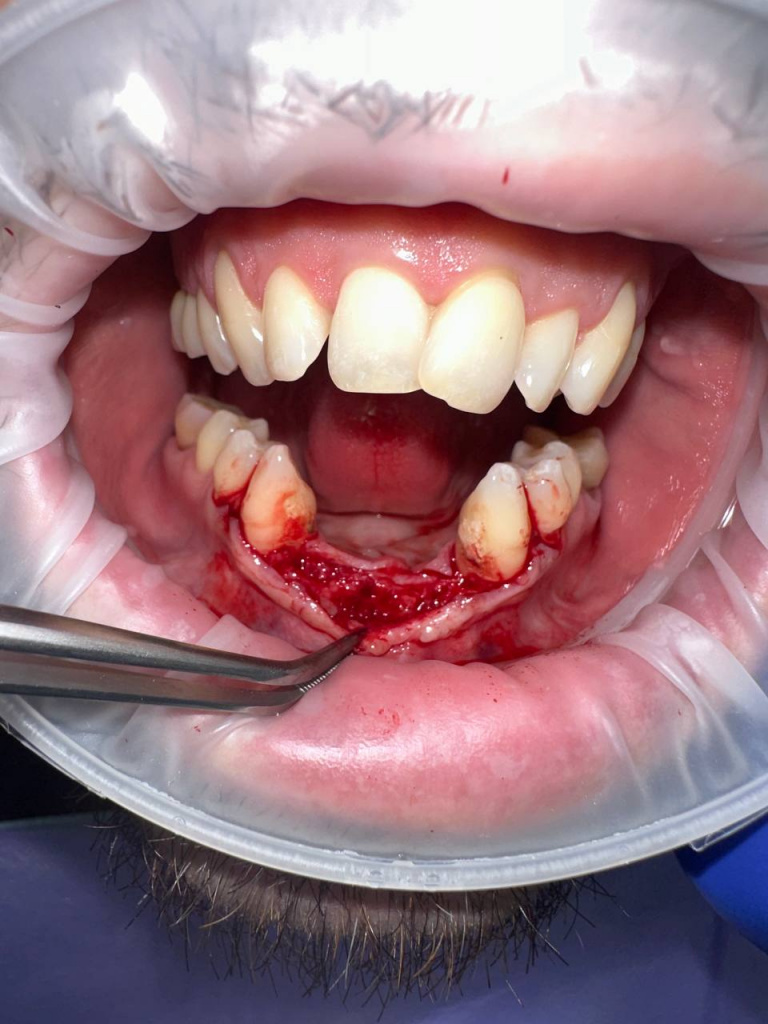

Уже много лет использую в своей практике имплантаты IMPRO. В этот раз мне предоставили линейку IMPRO Respect нового дизайна с широкими лепестками резьбы по отношению к телу имплантата. За счет чего получилось установить имплантаты в переднем отделе в узком гребне и с плохим костным предложением пациента. Ни разу не сталкивалась с осложнениями или проблем с имплантатми IMPRO Implantem. В этот раз не было исключением, была проведена операция через навигационный шаблон, имплантаты стабилизировались с хорошим торком. Хирургический набор и протоколы достаточно просты и удобны. Будем ждать ортопедической части, спустя месяц имплантаты стоят хорошо!

Пациент — мужчина 54 года.